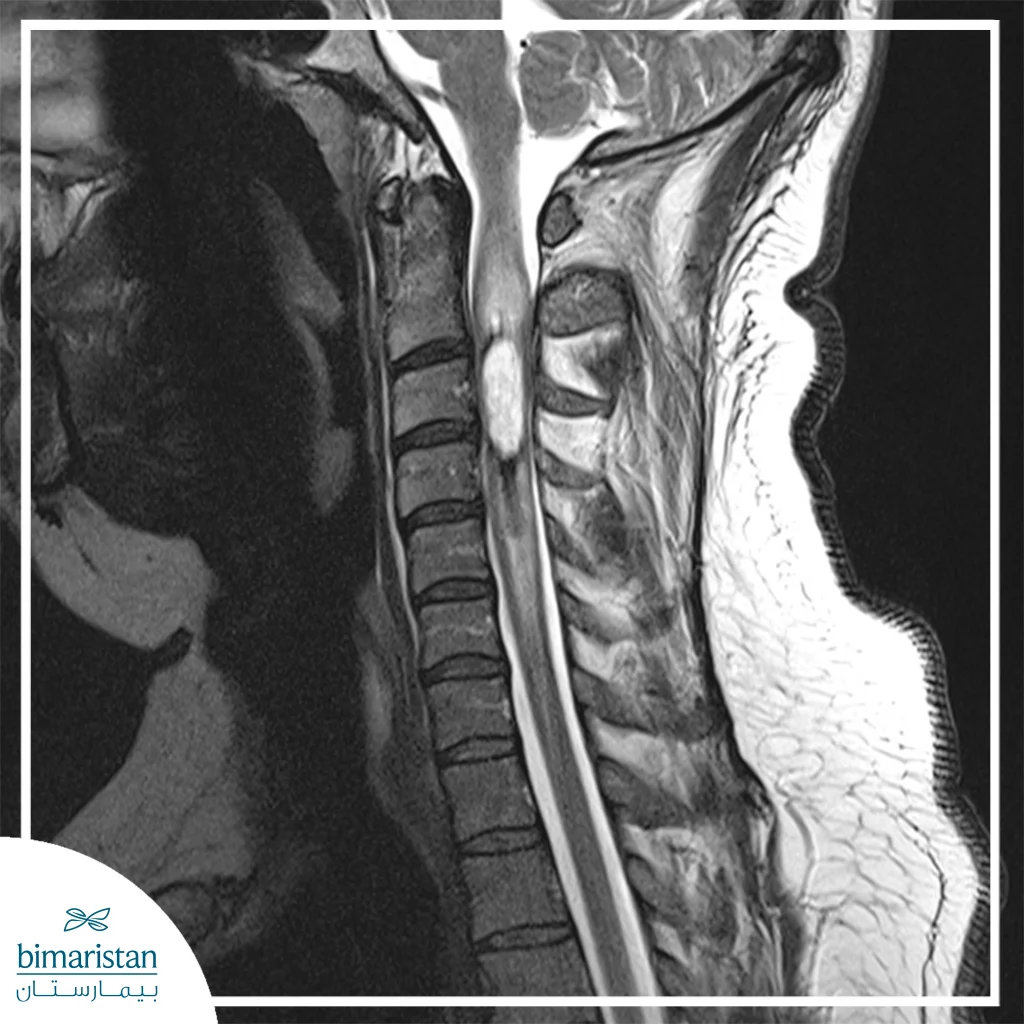

- Evaluation of the patient’s medical condition: A thorough evaluation of the patient’s condition using tests such as an X-ray or MRI helps determine the location of the tumor and how it affects the surrounding bones or nerves.

- Monitoring results and healing: After the stem cell injection, the patient is periodically monitored using X-rays or MRIs to ensure that the stem cells are doing their job of stimulating growth.